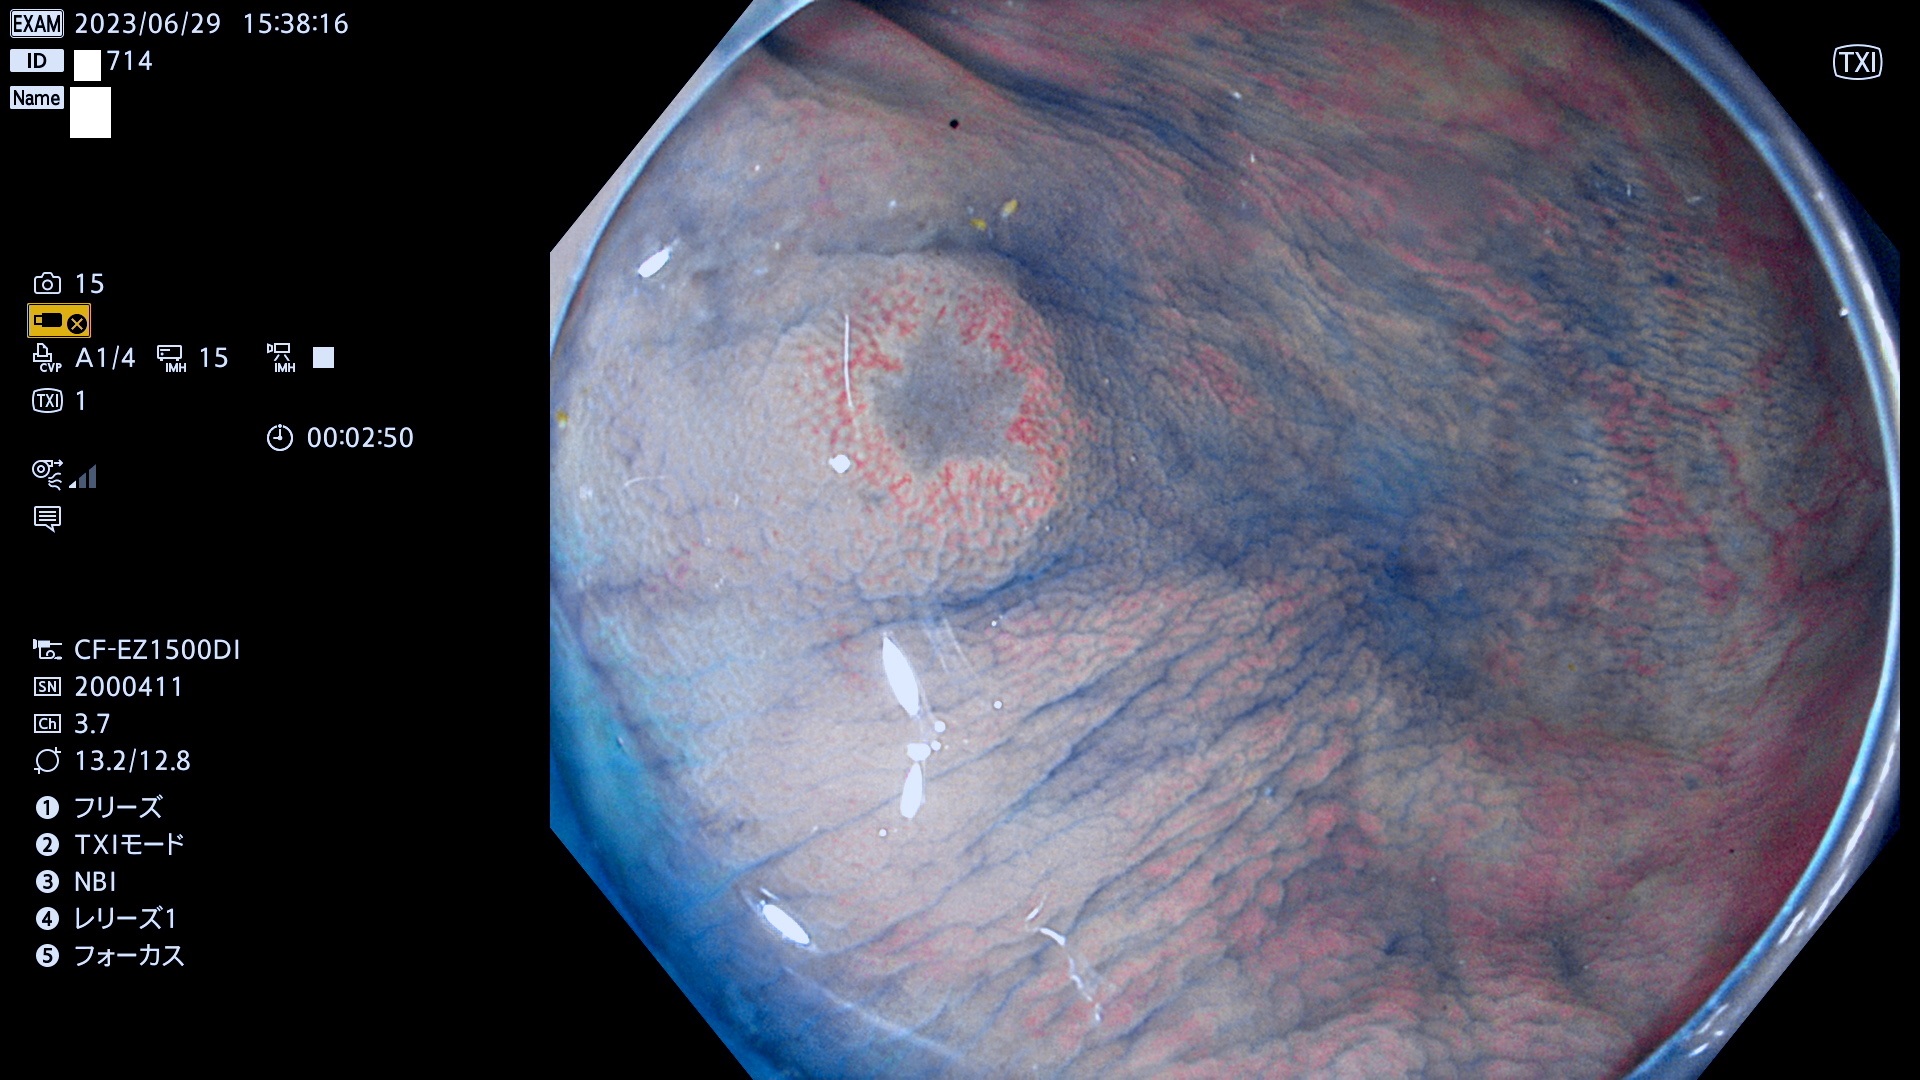

「表面型腫瘍」の中で、完全に平坦な物をUb、陥凹している物をUcと呼びます。平坦隆起型(Ua)よりも、発見が難しく危険な病変です。このタイプの発見率は「腺腫発見率」よりも、遥かに重要な意義があります。

抽出の対象期間 2023年6月29日(木)〜7月2(日)の4日間(48件の検査)8件